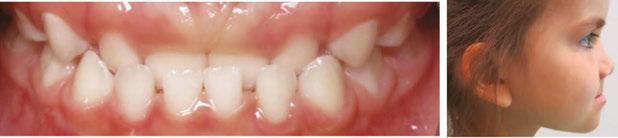

A pediatric-patient dedicated Sleep Medicine laboratory setting is difficult or impossible to find, setting aside what is considered the diagnostic gold standard, overnight PSG. Most screening questionnaires can be valuable as SRBD morbidity assessment tools and reliable for predicting increased risk. They are based solely upon identifying SRBD behavioral phenotypes known to be associated with suboptimal sleep hygiene (e.g., snoring, teeth grinding/bruxism, excessive bodily movements). The Sleep Clinical Record (SCR)15 is an exception because it relies on not only behavioral morbidity traits, but also some physical morbidity traits such as constrictive/retrusive and retrognathic jaw maldevelopments,16 which are known to be associated comorbidities with SRBD.17 Most of these physical traits can be classified as malocclusion phenotypes and generally are located within the interconnected craniofacial respiratory complex (CFRC)18 (Fig. 1) which was foreshadowed by Dr. LeRoy Johnson in the opening paragraph of

this review: ‘The face has evolved with the functions of mastication and respiration.’- L.J. 1921.

While the SCR goes further than most other screening assessment tools towards identification of some CFRC/SRBD co-morbidities, it is limited in its comprehensiveness. Ideally, in addition to screening for birth/perinatal history risk factors, such as pre-term birth,19,20 clinicians should have validated screening tools for identifying behavioral comorbidity traits, and for identification of physical risk phenotypes of the CFRC. The CHICAGO HEARTS screening tool combines these survey areas. (Fig. 2).

In a lecture held in 2018 at Boston University entitled ‘Sleep Disordered Breathing/Obstructive Sleep Apnea Symposium’,21 a new screening tool called C.H.I.C.A.G.O. H.E.A.R.T.S. (C.H.) had been introduced as potentially becoming the first validated screening device specifically designed to identify CFRC physical traits that can often be comorbid with SRBD. Several of these traits are listed within the C.H. acronym (Fig. 2). For instance, under the first letter ‘C’ are listed: Crossbite 22,23 Fig. 3 and Crowded Pharynx;24,25 ‘H’: Hyper-divergent growth (Fig. 4),16 Hypertrophic tonsils and/or adenoids;26,27 ‘I’: Incompetent lips;28 ‘C’: Constricted arches (Fig. 5);23,29,30 ‘A’: Airway anatomy (Fig. 6);22,31 ‘G’: Grinding teeth (bruxism)32 and Gonial angle excess;33 ‘O’: Overweight child34 and Obtuse nose-lip angle( NLA);35 ‘H’: Highly-vaulted palate;36 ‘E’: Ezcema-atopia37 and Eye appearance-venous pooling38 and scleral show;39 ‘A’: Anterior open-bite

(Fig. 8):40 ‘R’: Retrognathia (Fig. 9) (mandible16 and/or maxilla);41 ‘T’: Tongue posture,42 tie (tether),43,44 scalloping;45 ‘S’: Septal deviation46 and night Sweats (diaphoresis).47